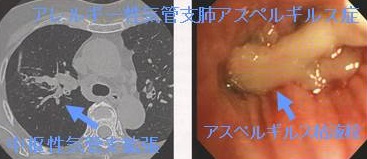

アレルギー性気管支肺アスペルギルス症(アレルギー性気管支肺真菌症)

アレルギー性気管支肺真菌症(allergic bronchopulmonary mycosis:ABPM)の最も一般的な原因菌は、アスペルギルス・フミガタス(Aspergillus fumigatus)で、アレルギー性気管支肺アスペルギルス症(allergic bronchopulmonary aspergillosis:ABPA)とも呼ばれます。カンジダ属、ペニシリウム属、スエヒロタケというキノコが原因の事もあります。

気管支喘息患者では、損傷して気道粘膜上皮障害にアスペルギルス・フミガタス(Aspergillus fumigatus)が生育しやすい。腐生したアスペルギルスに対する抗アスペルギルスIgG抗体が陽性化、免疫複合体となりⅠ型、Ⅲ型、Ⅳ型アレルギー反応を引き起こします。結果、粘液栓が形成され、喀痰中にアスペルギルス・フミガタス(Aspergillus fumigatus)を検出できます。

アレルギー性気管支肺アスペルギルス症

アレルギー性気管支肺アスペルギルス症は気管支喘息と間違えられる場合があります。症状および好酸球・IgE抗体増加が気管支喘息と同じためです。しかし、

1. 茶褐色の細長い粘稠な痰(粘液栓)が出る、喀痰培養でアスペルギルス・フミガタス(Aspergillus fumigatus) が検出

2. 抗アスペルギルス沈降抗体(旧)→アスペルギルスIgG抗体(ELISA法)(新)陽性、β-D-グルカン高値

3. 肺線維症・肺性心に進展する

点が気管支喘息と異なります。

胸部X線/CTで

1. 好酸球性肺炎による移動性浸潤影、すりガラス影

2. (※急性好酸球性肺炎とは異なる)

3. 気管支内のアスペルギルス粘液栓;高吸収の棍棒状陰影、手袋様陰影(finger-in-glove sign)

4. 末梢細気管支の粘液栓は小葉中心性粒状影

5. 中枢性気管支拡張

治療はステロイド投与。抗真菌剤併用しステロイド減量する治療も試みられていますが、耐性化と副作用から投与期間は慎重に決めねばなりません。